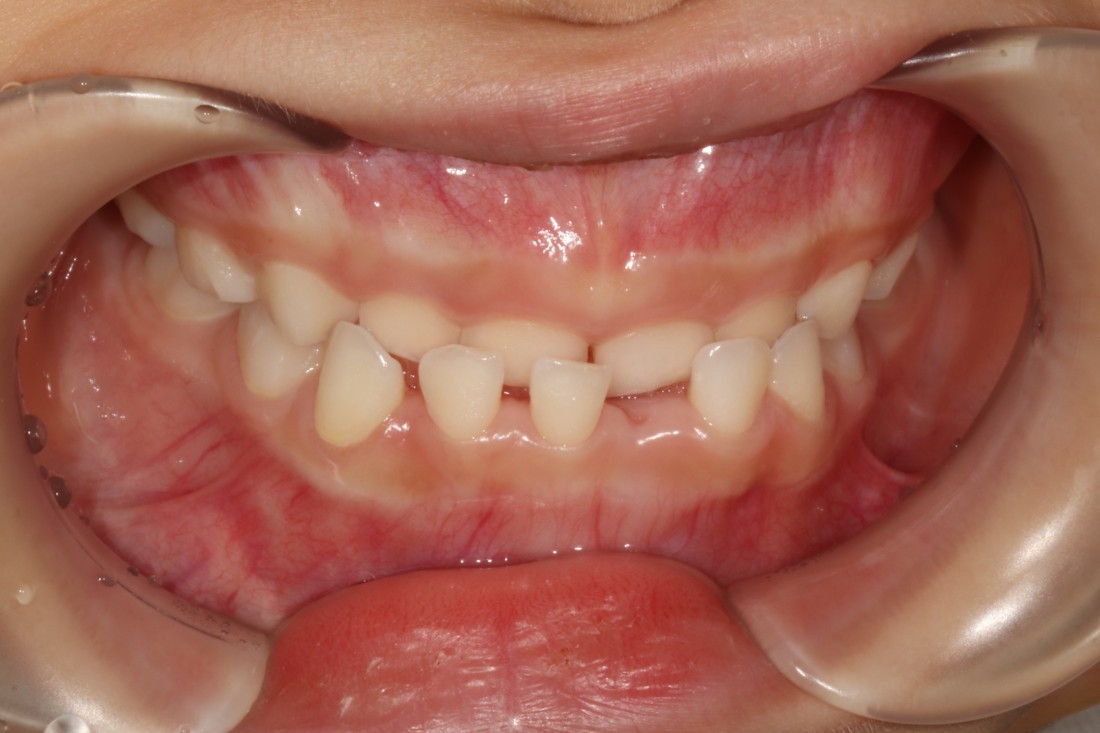

어린이부정교합의 케이스로

반대교합 / 과개교합 / 개방교합 정도로

크게 세 가지 유형으로 나누어서

각 케이스에 맞는 프리올소 교정장치 타입을

추천해드리고 있습니다.